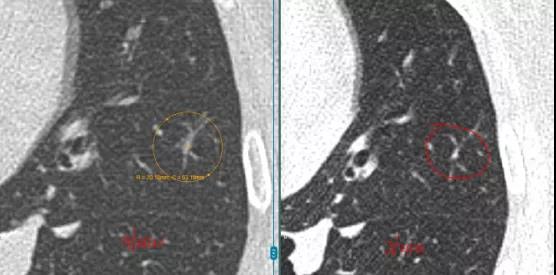

L教授:根据对患者病史和影像资料分析,其右肺上叶4mm磨玻璃结节与近期CT结果对比显示4年间大小未见明显改变,但该结节的密度稍微增高。

今年春天患者左肺上叶新出现的磨玻璃结节,影像上可以看到非常浅淡,对比近一次的检查来看,半年期间保持稳定,没有变大。

综上,我认为应重点监测的应该是右肺上叶4mm磨玻璃结节以及左肺上叶3mm磨玻璃结节。其中,4mm结节可能为惰性原发肺癌或炎性瘢痕,3mm浅淡结节可能惰性原发肺癌或炎症,但这些目前无法百分百确定,仍需继续随访观察。

L教授:虽然患者右肺上叶4mm结节密度有所增加,但程度非常小,所以尚不能做出确定的判断,仍需仔细监测;左肺下叶两枚结节由于属于实性结节,且超过2年都没有变化,故良性可能性非常高;左肺上叶浅淡结节为新增结节,性质不明,但该结节为恶性的可能性非常低。